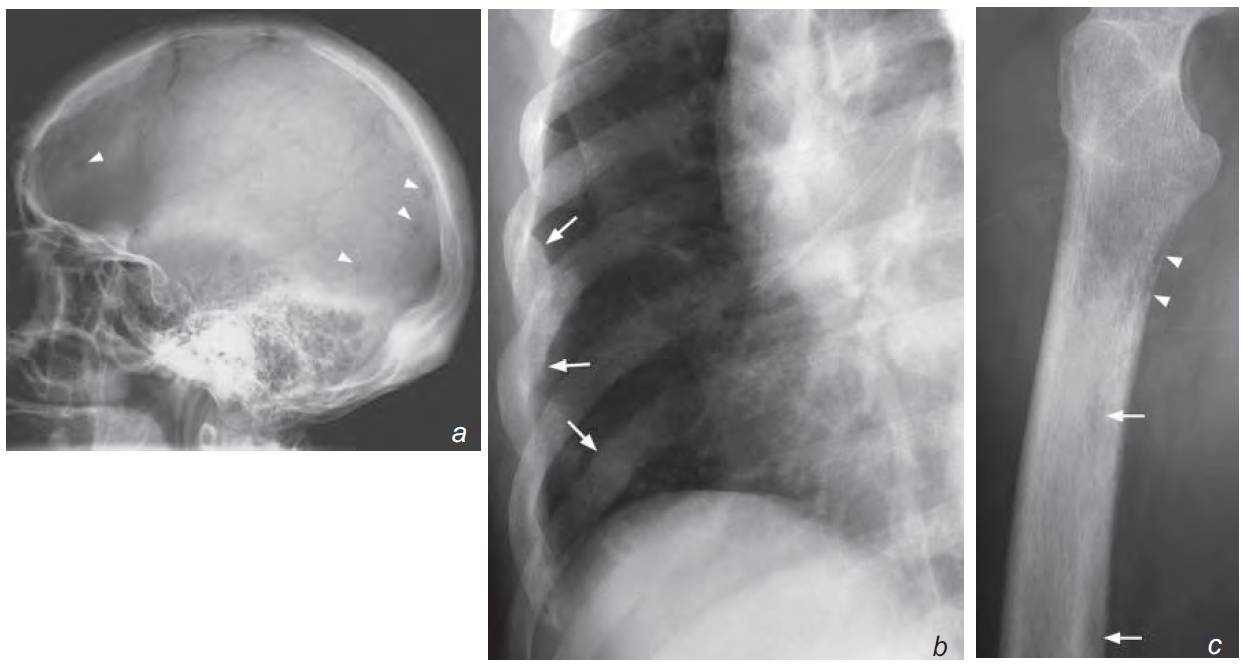

- Skull : Multiple well-defined lucent lesions affecting the cranial vault

- Ribs : Osteopenia and rib fractures

- Femur : Osteopenia, cortical thickening and focal cortical lucencies

a) Lateral view of the skull shows multiple small punched-out (well-defi ned) lucent lesions (arrowheads)

b) Oblique view of right lower ribs shows generalized osteopenia and rib fractures (arrows)

c) Lateral view of the proximal right femur shows generalized osteopenia with tunneling (arrowheads). More discrete lesions are also seen (arrows)